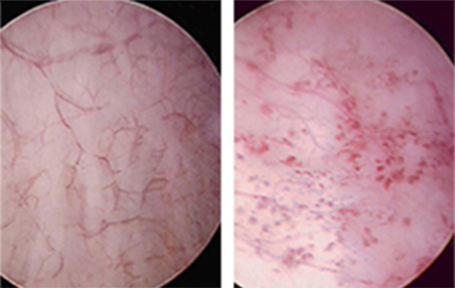

- La inflamación crónica produce microvasculopatía y ulceraciones (úlceras de Hunner en algunos casos).

- Se observan:

- Infiltrado linfocitario.

- Aumento de mastocitos.

- Engrosamiento de la pared vesical.

- Disminución de la capacidad vesical.